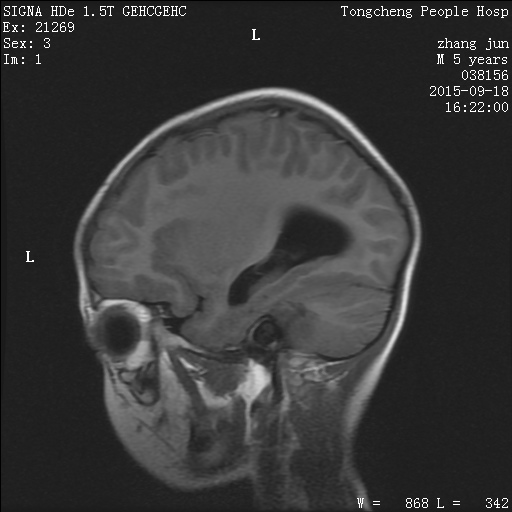

PED5207:M,6y。呕吐4天。

男,6岁。呕吐4天。 PE:心肺查体未见异常,腹部平软,未及包块,肠鸣音正常。 临床诊断:呕吐原因待查。 今行头部MR扫描,图像如下:

支持考虑后颅凹室管膜瘤并累及四脑室侧孔区。梗阻性脑积水。

1)第四脑室室管膜瘤累及左侧侧孔区。2)梗阻性脑积水。3)双侧上颌窦及双侧筛窦炎。